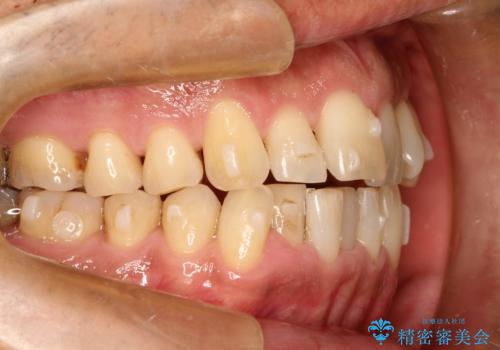

インビザライン invisalign ガタつきを治すマウスピース矯正

- 非抜歯・上顎臼歯遠心移動によるマウスピース矯正を計画した。

ガタつきを取り除くだけであれば非常に簡潔であるマウスピース矯正ですが、奥歯の位置関係の是正や、垂直的な歯の位置のコントロールなどが計画に含まれる場合、治療が難しくなってきます。